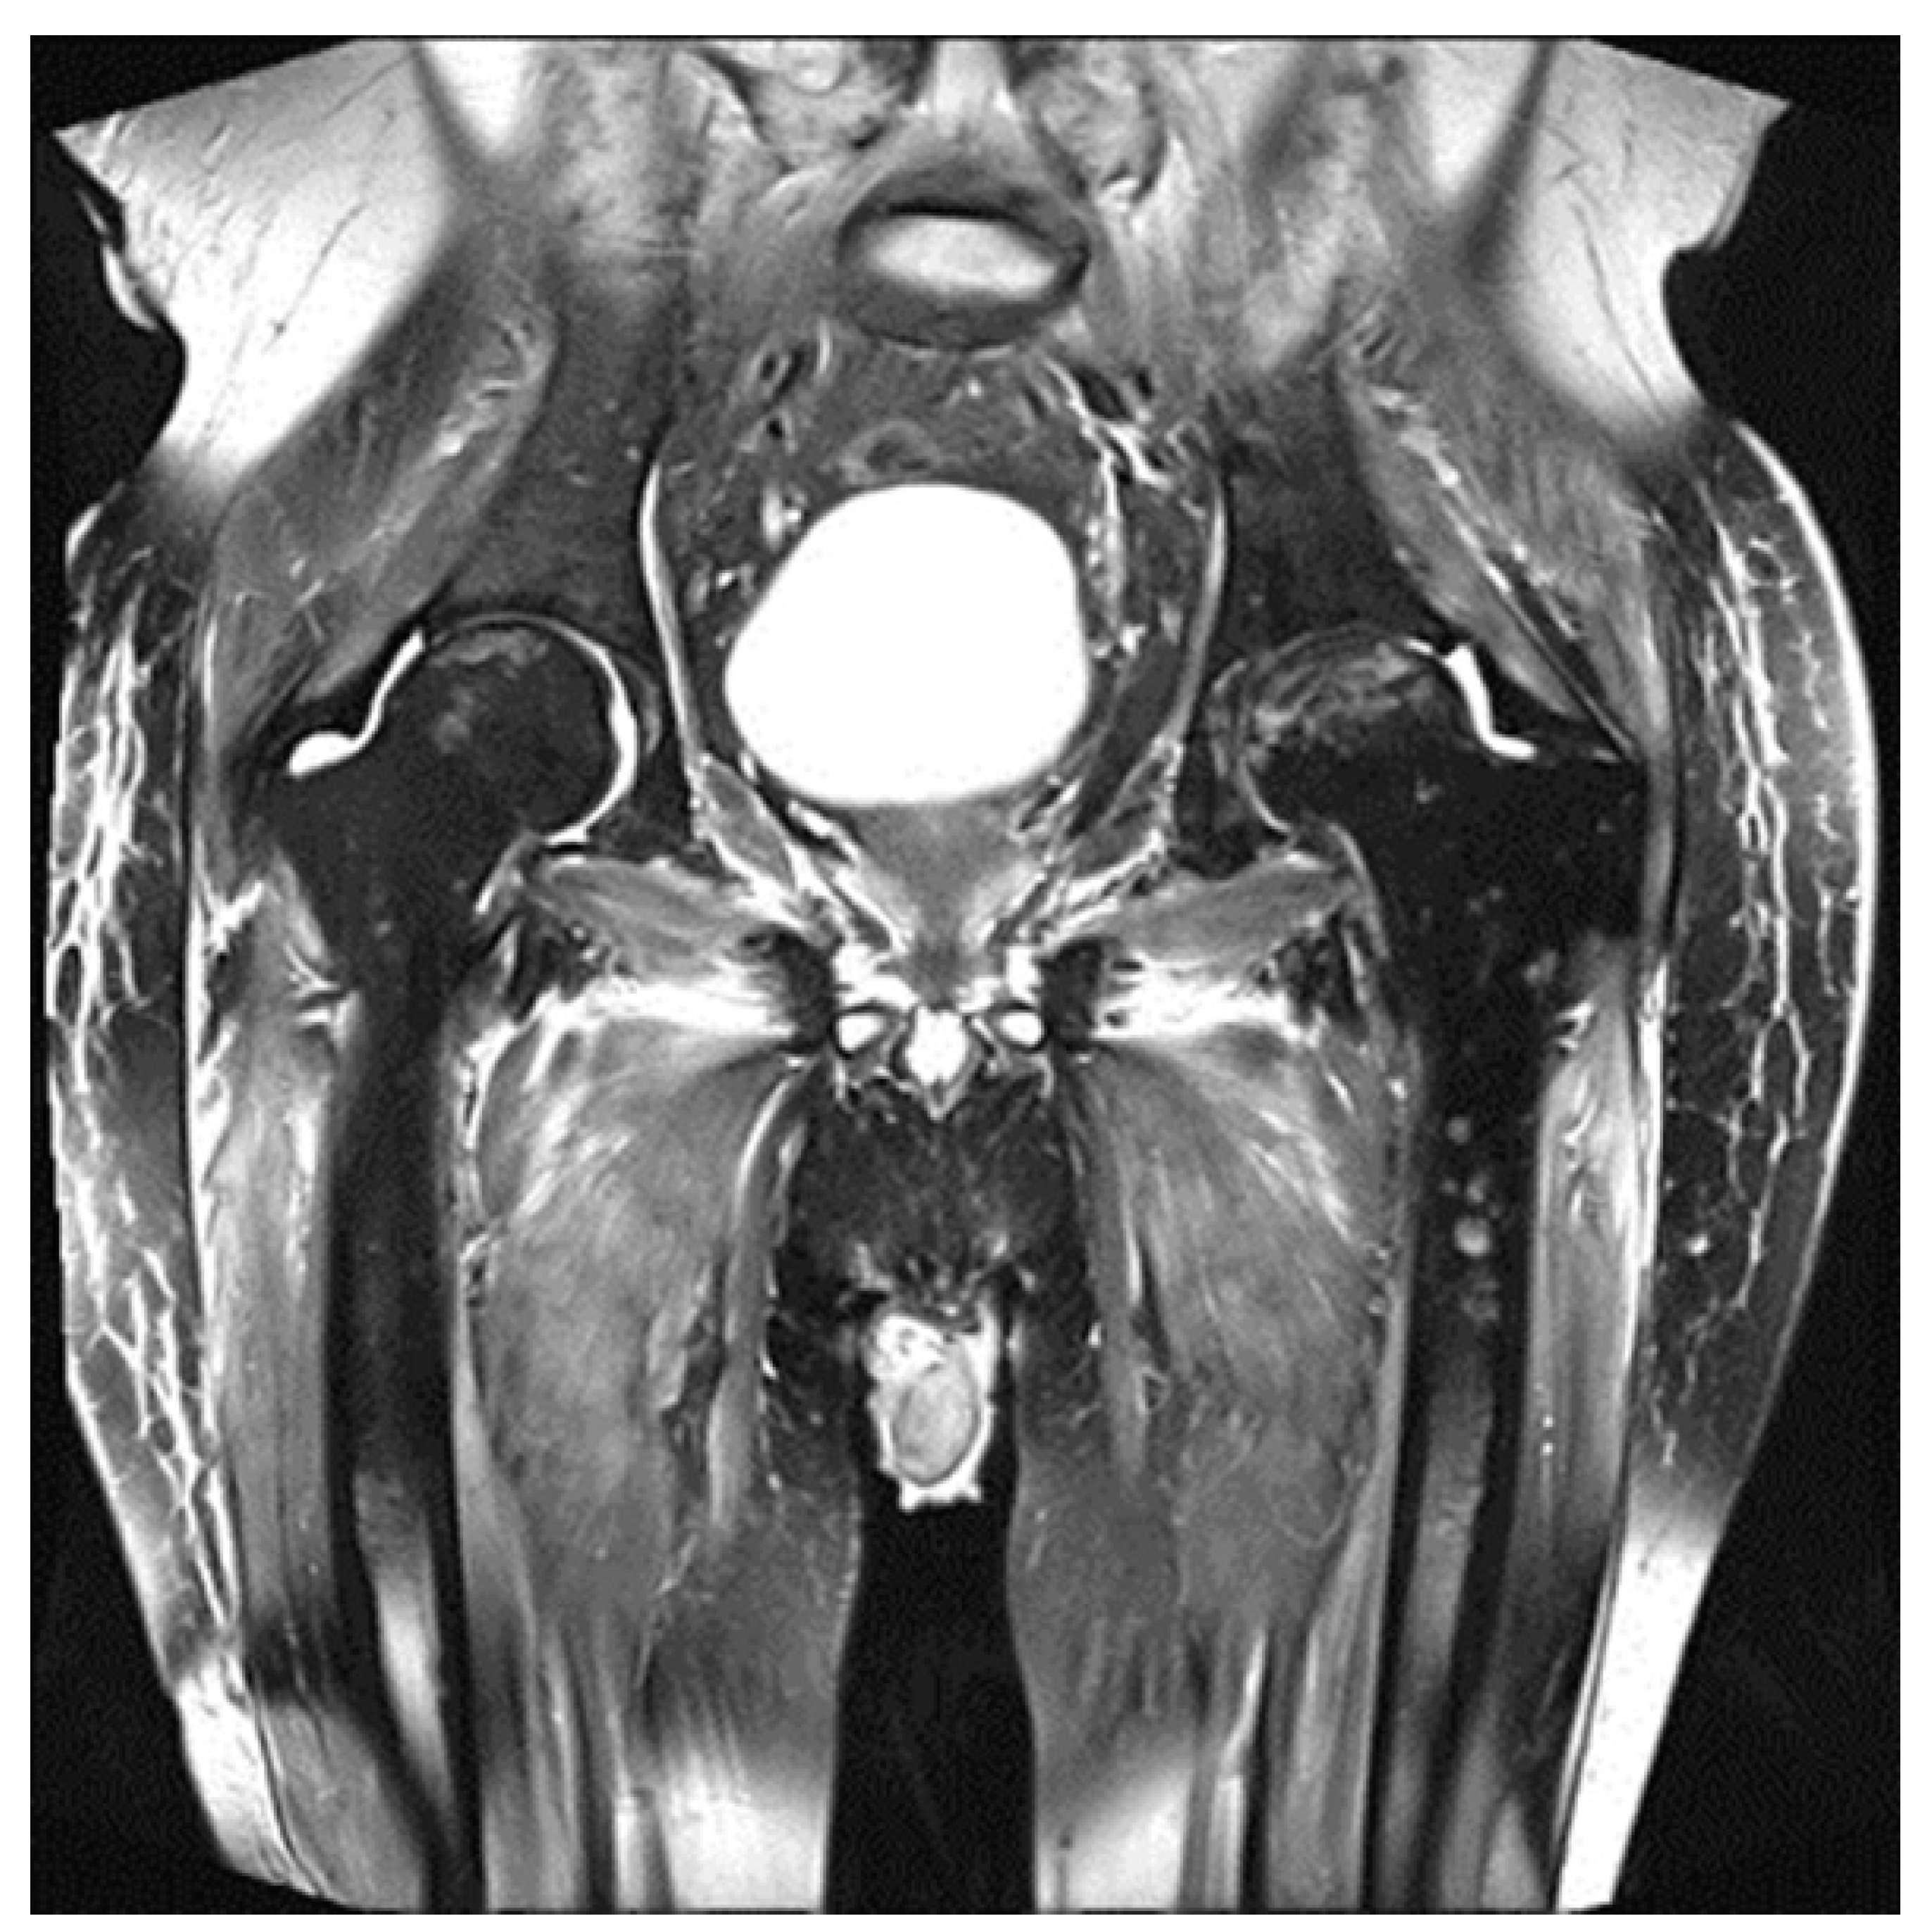

3. Value and Limits of MRI in Multiple Myeloma in the Post-Treatment Setting